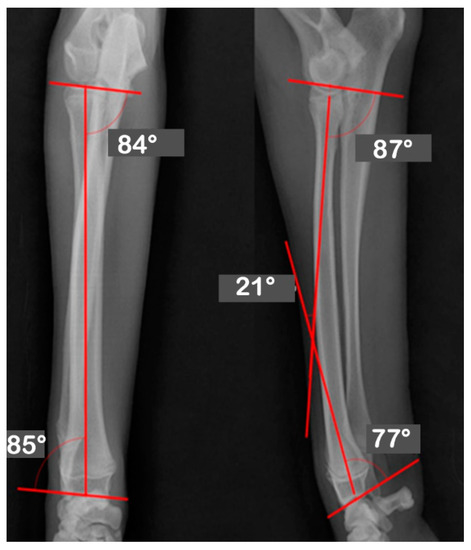

| JOA | Pre-OP | Post-OP | Target | Mean | Reference |

|---|---|---|---|---|---|

| Values | Values | ||||

| aLDRA | 57 | 85 | 85 | 86 | 85~87 |

| aCdPRA | 92 | 87 | 87 | 85 | 84~86 |

| aMPRA | 75 | 84 | 84 | 83 | 82~83 |

| aCdDRA | 62 | 77 | 77 | 77 | 76~78 |

| θ | 38 | 21 | 21 | 27 | 21~32 |